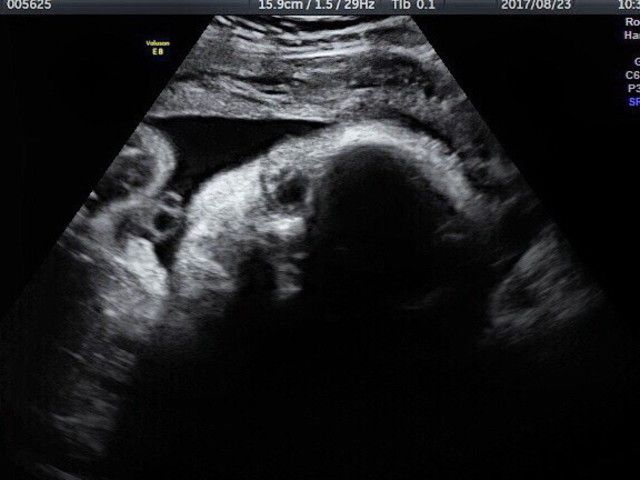

平面的な画像の2D超音波

「ほとんどの妊婦さんは、上記のようなモノクロで平面的な画像の写真をもらったことがあるはずです。これは2D(①縦軸②横軸の2次元)情報を組み立てて作られる画像。断面図のような形になるので、赤ちゃんの骨格や内臓の発達状況など、医学的に必要な情報をたくさん得ることができます。とはいえ、何が写っているのか判断するには専門知識が必要になるので、ママやパパ的にはわかりづらいことも多いようです」